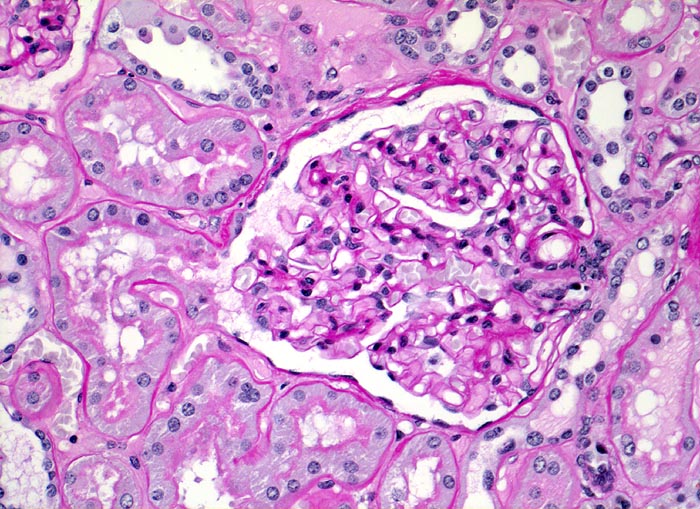

Im allgemeinen ist die Niere infolge von Glomerulumhypertrophie und Tubulushyperplasie vergrössert und derb, die Oberfläche ist granuliert. Bei schwerer Atherosklerose und fortgeschrittener Niereninsuffizienz kann die Niere auch normal gross oder verkleinert sein. Die Kombination von nodulärer Glomerulosklerose, hyalinen Schlingenkappen (=Proteinthromben in den Glomerulumschlingen (> 1916)) oder Kapseltropfen (> 1907) und Arteriolosklerose in Vas afferens und efferens ist beweisend für eine diabetische Nephropathie. Jede einzelne Läsion für sich genommen ist aber unspezifisch. Eine noduläre Glomerulosklerose kann auch vorkommen bei membranoproliferativer Glomerulonephritis (> 2652), Leichtkettenglomerulopathie oder Amyloidose (> 2019). Der nodulären Glomerulosklerose geht bei Diabetikern eine diffuse Glomerulosklerose (> 1906) voraus. Dabei zeigen die glomerulären Basalmembranen und das Mesangium eine progrediente gleichförmige Verbreiterung. Bei der nodulären und diffusen Glomerulosklerose handelt es sich aber wahrscheinlich um zwei pathogenetisch unterschiedliche, sich überlagernde Krankheitsbilder. Typisch bei Diabetikern ist im Unterschied zur arteriellen Hypertonie die Arteriolosklerose von Vas afferens und efferens (> 1911) und oft auch der Vasa recta. Intrarenale Arterien können eine Atherosklerose mit Atheromen zeigen. Subendotheliale Proteinablagerungen teilweise mit Verschluss der Glomerulumschlingen (Schlingenkappen) und knotige Proteinablagerungen in der Bowman'schen Kapselbasalmebran (Kapseltropfen) gehören zu den sogenannten exsudativen Läsionen (> 1919) (> 1920) der diabetischen Nephropathie und führen zu Synechien sowie zur globalen Glomerulosklerose. Gleichzeitig mit den Glomerulumveränderungen treten tubuläre Basalmembranverbreiterungen auf, später eine Tubulusatrophie und interstitielle Fibrose mit Begleitentzündung. Auch die Basalmembranen der peritubulären Kapillaren sind verdickt.

• Verbreiterung des Mesangiums mit Ausbildung von Knoten(noduläre Glomerulosklerose).

• Exsudative Läsionen: Hyaline Schlingenkappen (Proteinthromben in Glomerulumschlingen, im virtuellen Präparat nicht sichtbar) und Kapseltropfen (Proteinablagerungen im Bowman’schen Kapselraum).

• Arteriolosklerose von Vas afferens und efferens (Gefässwandhyalinose durch Ablagerung von Plasmaproteinen und Lipiden in der Gefässwand).

• Verdickte Basalmembranen der peritubulären Kapillaren.